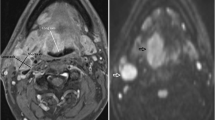

The ROIs were placed by a radiologist (3 years’ experience) under the supervision of another radiologist (21 years’ experience). The first 24 participants were also independently analysed by a further radiologist (5 years’ experience) to assess for inter-observer agreement. ROIs were placed individually within the primary tumour and/or the largest pathological lymph node (Figs. 1, 2) using OsiriX v8.0.2, open-source Mac-based medical image processing software. ROIs were placed on the pre-treatment, 6-week (ADCmean6) and 12-week (ADCmean12) post-treatment MRI studies using the DWI b = 800 s/mm2 map, but with access to other MRI sequences. When a focus of increased DWI signal was not evident on post-treatment images, a standardised 6 mm diameter ROI was placed at its original location. An ADC map was generated from the b 100 and b 800 s/mm2 images. A ROI was also placed within the cervical spinal cord on the ADC map as a reference.

A HPV negative participant with a partially necrotic left level 2 lymph node. a T1w post gadolinium axial image pre-treatment demonstrates the lymph node (arrow). b b = 800 s/mm2 map from DW-MRI pre-treatment indicating the lymph node ROI as the increased DWI signal whilst avoiding the necrotic area. c T1w post gadolinium axial image at 12 weeks post-treatment demonstrates the lymph node to be of reduced size (arrow). b b = 800 s/mm2 map from DW-MRI at 12 weeks post-treatment indicating the lymph node ROI as the increased DWI signal. e 18F-FDG PET-CT study at 12 weeks post-treatment demonstrating the 6 mm VOI at the site of mild 18F-FDG uptake in the lymph node

A 6 mm diameter volume of interest (VOI) was placed by a radiologist (3 years’ experience), under the supervision of another radiologist (16 years’ experience). VOIs were placed at the site of most intense FDG uptake within either the primary lesion and/or the largest lymph node, which were matched to the ROI placed for the MRI analysis (Figs. 1, 2). If there was reduced uptake on the post-treatment images relative to background, a 6 mm VOI was placed at the same site as the post-treatment MRI ROI. If necrosis was identified within a lesion, the area of necrosis was excluded. The SUVmax was calculated with semi-automated software on a Hermes workstation (Hermes Gold 3, Stockholm).